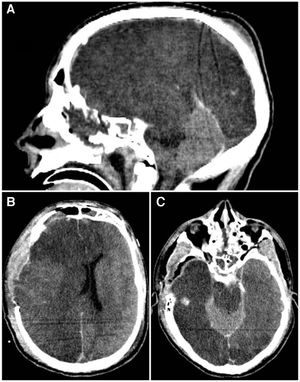

El primer paciente, de 29 años, presentó un politraumatismo tras una caída desde 2,5 metros. Al ingreso, presentaba Glasgow 3, pupilas anisocóricas y ausencia de respuesta motora al dolor. La tomografía de cráneo (TC) inicial evidenció hipodensidad supratentorial difusa, desdiferenciación de la sustancia gris-blanca, borramiento de surcos, colapso de cisternas peritroncales y un cerebelo hiperdenso en cortes sagitales. El paciente falleció tras 4 días de internación por shock refractario (fig. 1).

A) TC de cerebro corte sagital que demuestra el signo del cerebelo blanco, asociado a hipodensidad del tronco encefálico. B) TC de cerebro corte axial que evidencia desviación de la línea media por edema hemisférico derecho. C) TC de cerebro corte axial con evidencia de hiperdensidad relativa del cerebelo en relación a los hemisferios cerebrales.